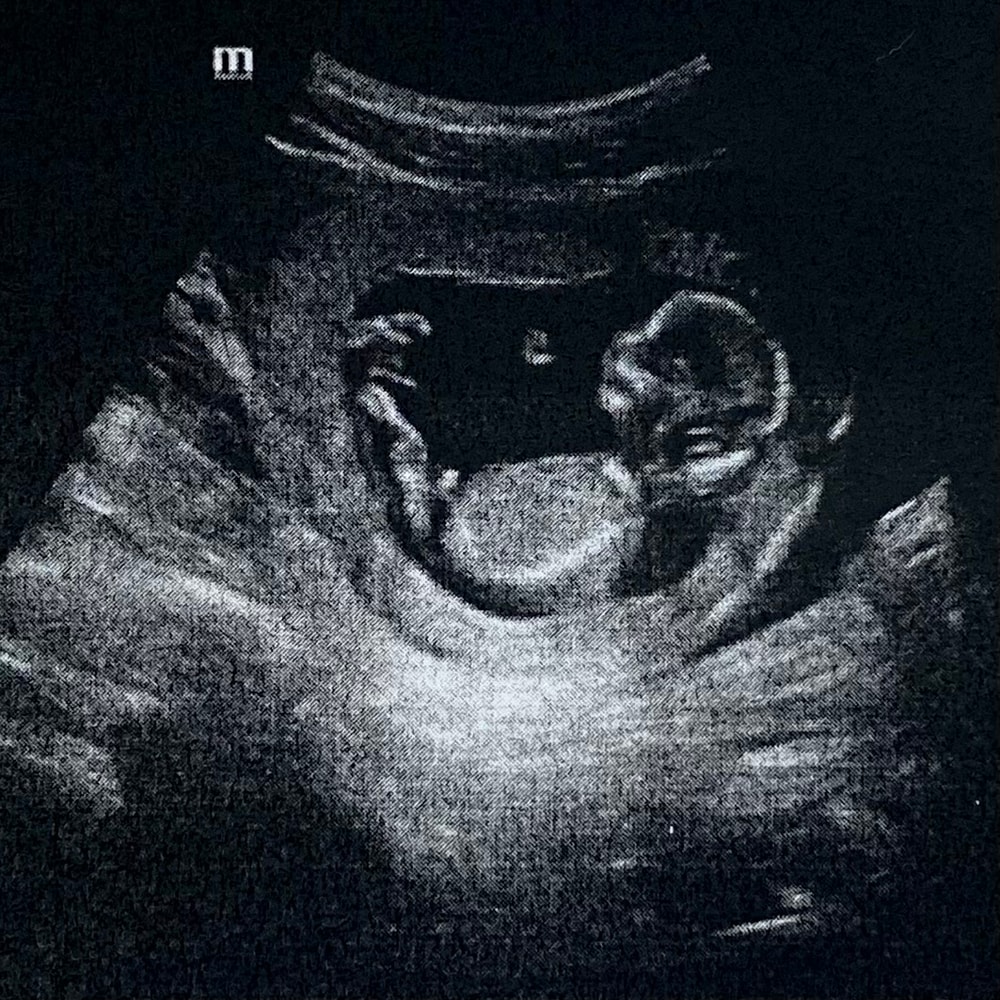

Фото УЗИ (13 недель)

😍Вот он, малыш размером с персик 🍑

Малыш не спал (как на первом УЗИ в 12 недель), двигал ручками, ножками, даже икал). Видели как он что-то жуёт, открывает и закрывает ротик). Любимый всё записал на видео😍. На снимке малыш вытянул ножки, помахал ручкой🥰, вторая рука была за головой (типа привет, я тут загараю😅). Снимки распечатали на обычной бумаге А4, вместе с заключением (хотелось бы отдельно на специальной плёнке для УЗИ, но у них её не было).

📝Копчико-теменной размер плода 68.2 мм..

📝Толщина воротникового пространства плода 1,5 мм (N до 2,39 мм )

📝Кости носа визуализируются,длина 2,2 мм(N от 1,69 мм).

📝ЧСС плода 153 ударов в мин.

📝По анатомии плода (ручки, ножки и тд) всё в норме.